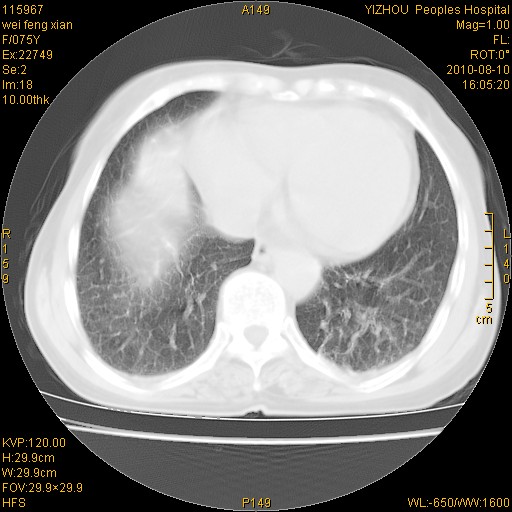

双肺间质增生并右肺上叶炎性改变,不除外右肺上叶结核病肺内播散

考虑慢支伴右上肺慢性感染可能性大,建议结合临床排外尘肺可能。

考虑尘肺可能性大.

考虑右肺上叶炎症合并双肺结核可能性大,建议上传纵隔窗ct图片。

双肺结核可能性大

考虑尘肺并结核;右上肺支气管扩张!

结核、尘肺、支气管肺泡癌都不能除外

右肺上叶继发性肺结核伴肺内血型播散!

考虑右肺上叶继发性肺结核伴两肺播散。